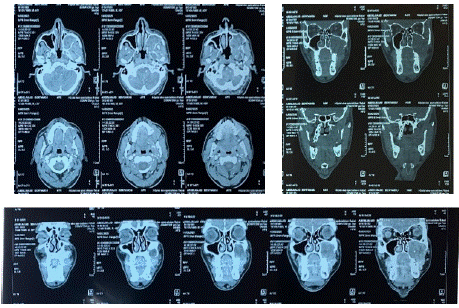

A CT scan of the facial skeleton was performed, revealing a lytic lesion of the left maxillary bone with a multilobulated appearance and a soap bubble image. After evaluation of all the examinations conducted, the diagnosis of a benign but locally invasive ameloblastoma was made (Figure 3).

Figure 3: Facial CT scan showing the left maxillary tumor.